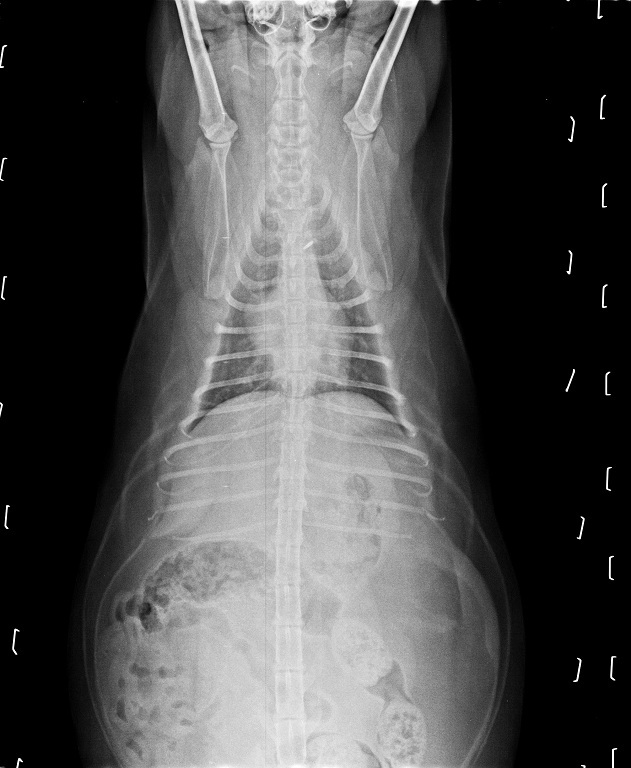

在拍X光照檢視後確認並沒有誤吃奇怪的東西,

肺部雖然有點混濁的情況但不是太嚴重,

並且再拍第二次X光照時發現已經到了肺炎的程度,